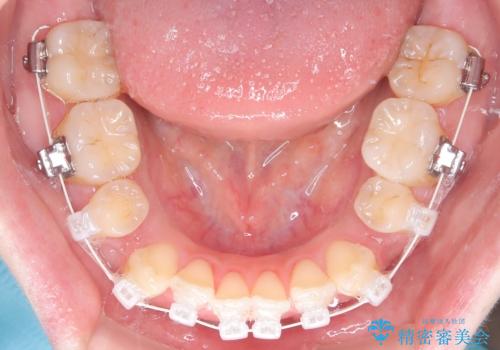

- 前歯のガタガタや八重歯の位置の乱れが気になっていた患者様に対して、ワイヤー矯正を行いました。矯正の過程で、スペースを確保するために上下左右の小臼歯を抜歯し、歯全体のバランスと機能性を考慮しながら理想的な歯列に仕上げました。

治療後は、前歯の位置や噛み合わせが整い、見た目も機能面も大きく改善されました。きれいな歯並びを得ることができ、患者様にも非常に満足していただけました。

抜歯によって確保したスペースを活用し、効率的に歯列を整えました。前歯のガタガタと八重歯が解消され、自然で美しい仕上がりを実現しました。